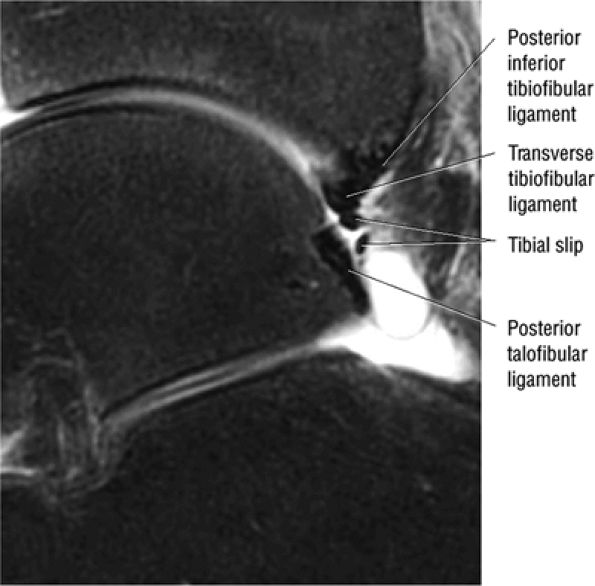

The syndesmotic ligaments consist of the anterior syndesmotic or anterior inferior tibiofibular ligament and the posterior syndesmotic or posterior inferior tibiofibular ligament, the interosseous membrane, and the transverse tibiofibular ligament.

The transverse tibiofibular ligament represents the posterior labrum of the ankle and projects inferior to the posterior tibial margin.

The tibial slip is the posterior intermalleolar ligament.